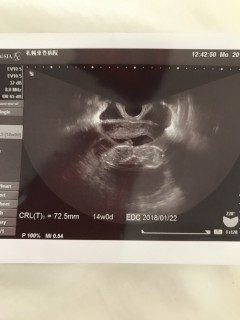

2週間前は44.0ミリで今回はちょっと大きめ72.5ミリ14w相当の大きさに成長! 経膣エコーだった為先生に大きくて写らないわーと言われ微妙なエコー写真。 元気ならいいかぁ^^ この1週間後くらいに胎動らしきものが! 1人目の時より4週早く分かり半信半疑でしたが日に日に大きくなってく胎動にうれしい反面たくましく育ってるなぁと感心中です^^